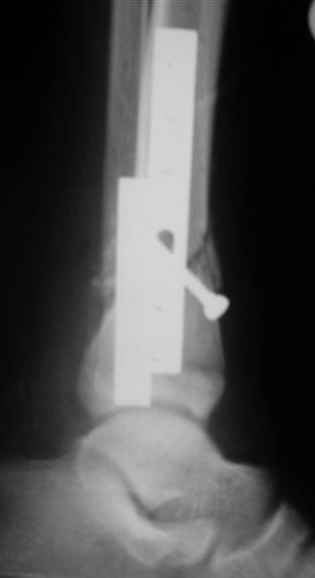

Помятуя наш недавний разговор о фиксации м.б. кост, высылаю послеоперационные картинки..

Напомню- разбирали случай 17 летнего молодого человека перелом дист тиб.фиб. хирургия после 3 недель с момента травмы( безуспешные попытки закрытой репозиции) Раны заживают первичным натяжением, занимается физиотерапией, пока никаких проблем не наблюдается

Согласный я с тобой:-)) есть остаточная вальгусная деформация (по снимку видно перекрывание дист. фрагментом б.б по латеральной поверхности проксимальноо фагмента на 2-3 мм и наружная лодыжка репонирована с укорочением, судя по прямой проекции. Необходимость использования интраоперационно дистрактора была бы оправдана (вручную было непросто *вытянуть* дистальный отломок.)

На мой взгляд, Ваша демонстрация неожиданно добавила перцу. Если память мне не изменяет, я говорил об отсутствии показаний к остеосинтезу малоберцовой.

Сейчас можно заикнуться о вредности этой манипуляции с точки зрения риска фиксации в неправильном положении, как это получилось у Вашего пациента. Сначала фиксировали большеберцовую, и надо было на этом остановиться, ин май хамбл опиньон. Потом при закручивании винтов на мощнейшей второй пластине сустав увело на вальгус. С учетом того, что пацану всего 17, я бы удалил пластину с малоберцовой и попытался тем или иным способом устранить смещение, пока не срослось.

Все так и не совсем - последовательность процедуры( я уже, кажется, упоминал)открыл зону перелома б.б., оценил мобильность фрагментов при очевидном смещении - отрепонировать вручную не получилось и понятна причина. Открыл область перелома м.б. отрепонировал( как мне показалось вполне адекватно) и фиксировал пластиной. ПРи ревизии зоны перелома б.б. положение фрагментов улучшилось, но сохранялось остаточное смещение дистального фрагмента кпереди хоть и незначительное, которое устранил и фиксировал межфрагментарным винтом, далее пластина. Конечно, следовало интраоперационно проконтролировать РГ, откровенно говоря, не ожидал, что постоп контроль будет так выглядить, показалось , что достигнутая репозиция вполне адекватна.....

Согласен с вашей рекомендацией (пока парень отпросился на выходные домой, а по возвращении будет разговор) Кстати ваш аргумент в пользу важности адекватной репозиции м.б. .... Поскольку оставшийся вальгус ничем , кроме, как укорочением м.б не объяснить - для ревизии приготовлю дистрактор.